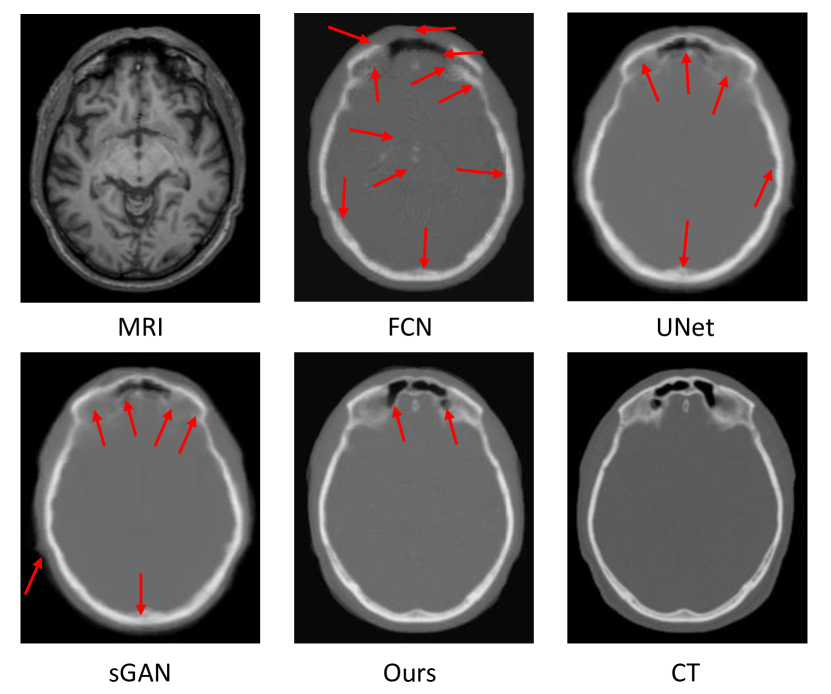

3.3 Comparing with Other Methods

To qualitatively compare the synthetic target image by different methods, we visualize the generated target image with the ground-truth target image in Fig. 4. We can see that the proposed algorithm can better preserve the continuity, coalition and smoothness in the synthetic results, since it uses both global and local adversarial learning constraints in the image patch as discussed in Section  2.1. More importantly, the tumor region of generated T1 MRI can recover much more details than other methods, and thus looks much closer to the real T2 MRI compared to all other methods. We argue that this is due to the difficult-region-aware attention mechanism which reweight more on the recognized hard-to-synthesis regions, i.e., tumor regions.

Refer to caption

Figure 4: Visual comparison of MR image, the estimated CT images by our method and other competing methods, and the ground-truth CT image for the typical brain tumor cases. Red arrows mean poorly synthesized regions.